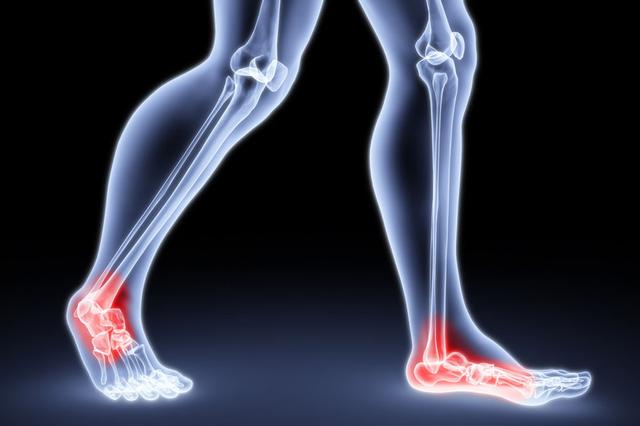

从一方面来说,人类是弱小的,容易生病,容易受伤,但从另一方面来说,人类也是强大的...